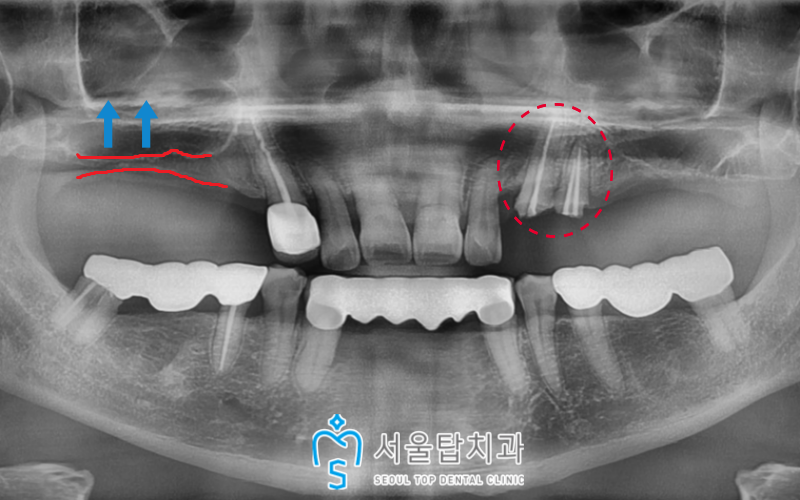

파노라마 사진을 촬영하여

치료계획을 수립해보았습니다!

🦷 왼쪽 위 🦷

치아머리가 부러진 송곳니(#23)와

첫 번째 작은 어금니(#24)는

발치 후 기존 상실된 부위와 함께

임플란트 식립을 계획하였습니다.

🦷 오른쪽 위 🦷

기존 상실된 부위로,

임플란트 식립을 계획하였는데요.

큰 어금니가 식립되는 자리에는

잇몸뼈가 너무 부족하여

상악동 거상술 + 뼈이식을 동반한

수술이 필요하였습니다.